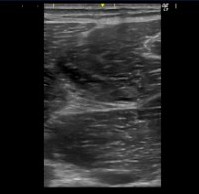

• 超音波検査:筋線維の連続性の乱れ、血腫(血溜まり)の有無、損傷範囲の特定

*筋内の黒い部分が損傷部位である。